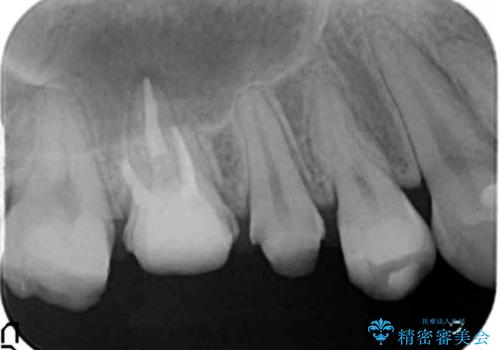

歯周外科を行い歯ぐきの整備を行うセラミック治療

銀歯周囲の虫歯再発や、歯ぐきよりも深い虫歯、根尖性歯周炎と言った複合的な問題を、

歯周外科、精密根管治療、セラミック治療を行い、妥協のないセラミック治療を計画します。

虫歯の再発可能性を限りなく低く抑えるためには、虫歯の徹底的な除去を行ったのちの精度の高いセラミック治療が必須です。

今回の治療では歯ぐきの問題を解決するため、歯周外科を行いました。